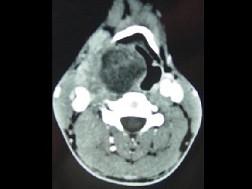

问题 男,41岁,右侧咽部不适两年余,有异物感,声音嘶哑,CT如图所示,最可能诊断为 ( )

选项 A、小唾液腺瘤 B、咽旁神经鞘膜瘤 C、咽旁转移癌 D、咽旁淋巴瘤 E、颈动脉体瘤

答案 B